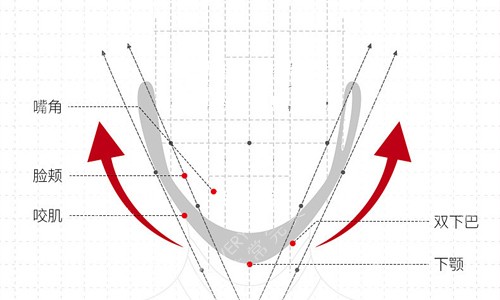

1个月时能吃软面条,2个月能啃苹果,3个月朋友见我头一句话是:你打了什么神仙针?脸小了一圈还没凹!现在6个月,拍照终于敢侧着脑袋,同事说我从职场御姐变温柔小姐姐。更惊喜的是咬合变好了,以前吃排骨总咬到腮,现在啃玉米都利索。

很多人问我双颚手术疼不疼风险大不大,我想说:疼痛是暂时的,自卑才是一辈子的。但一定要选能做正颌的医生——罗医生做过1000+台颌面手术,连截骨角度都更好到度,这才是富有经验的底气。我术前特意查了他的执业证书,是口腔颌面外科副主管医师,和普通整形医生的资质完全不一样。